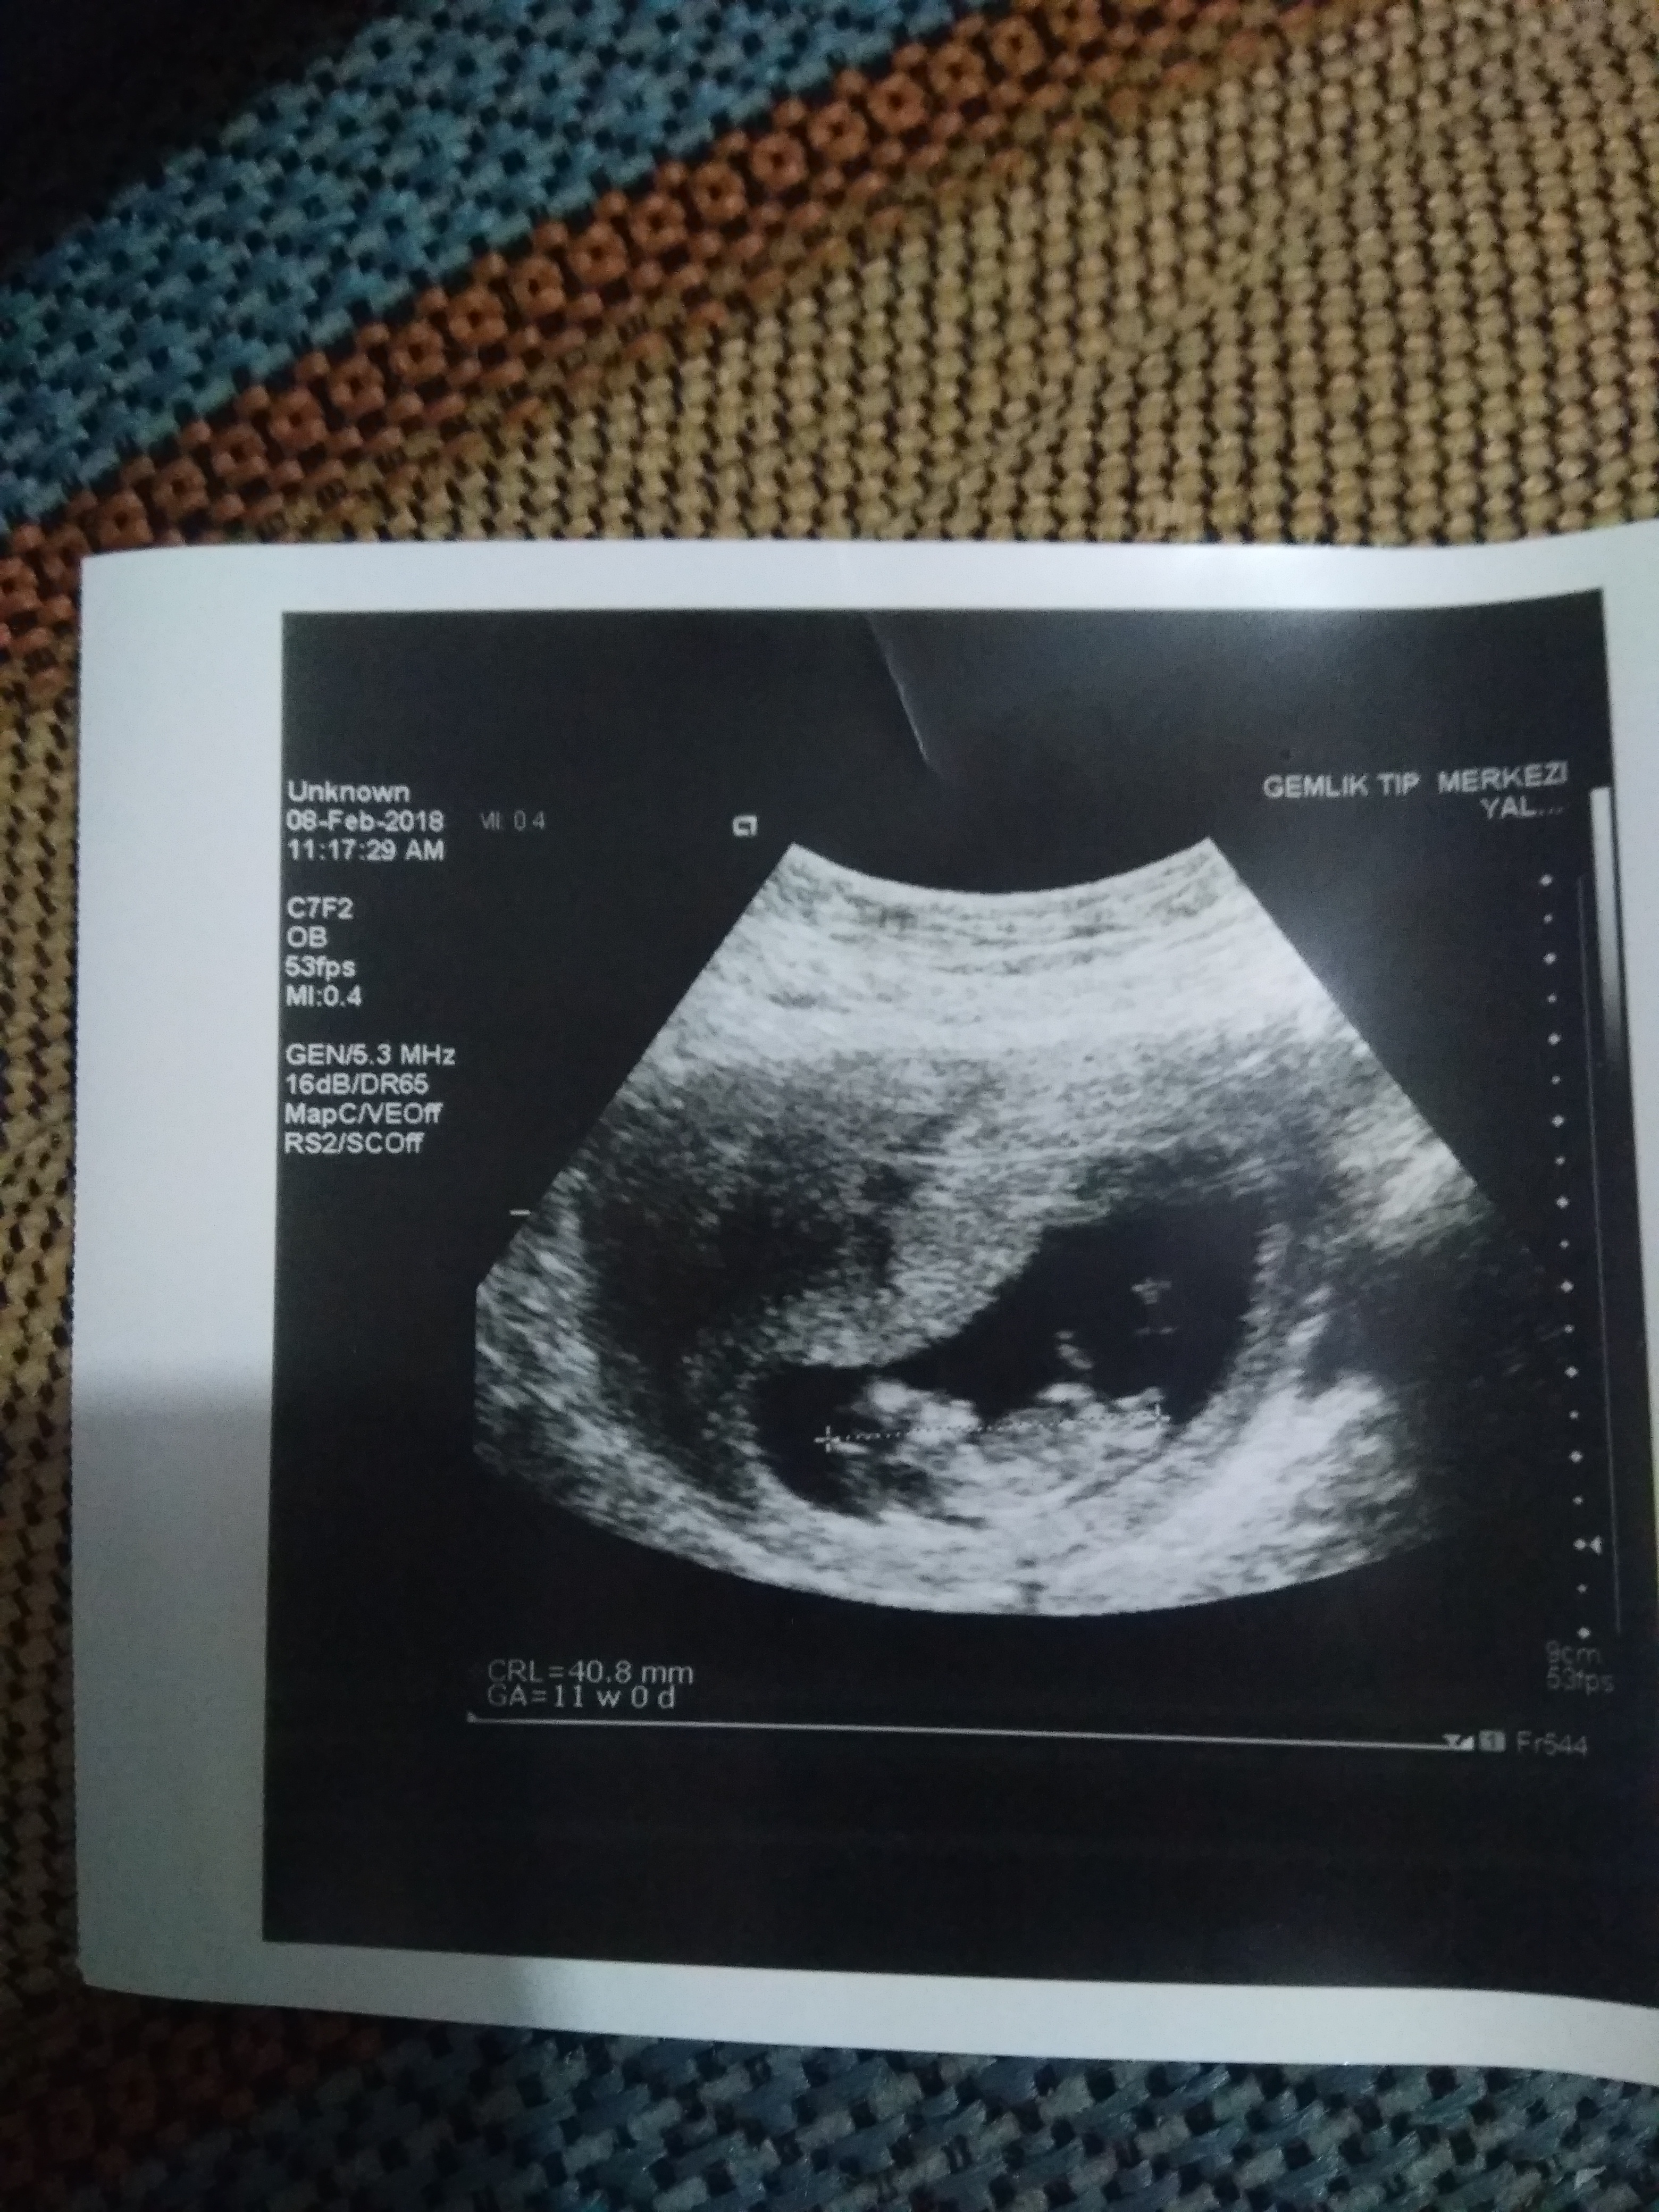

Selam kızlar gerek nub teorisine göre gerek ise çin takvimi olabilir ne şekilde olursa olsun ben bebeğimin cinsiyetini merak ediyorum. Henüz küçük görünmüyor da siz bişey diyebilir misiniz size göre bebeğimin cinsiyeti ne kızlar ?

Merhaba, nub teorisi ile cinsiyet tahminin de bulunurken şunu hep belirtiyoruz '' Tahmin de yanılma olma ihtimali yüksektir '' Ultrason muayenesi yapan hekimler bile yanılabiliyor. Ayrıca hekimler usg muayenesin de canlı görüntüye göre değerlendirme yapıyor. Sizlerin yüklemiş olduğu görsel anlıktır. Bebeğinizin cinsiyetini gebeliğin 17-18 ve 20. haftaların da net olarak öğrenebilirsiniz. Yüklemiş olduğunuz görsel de nub çıkıntısı tam belli değil , emin olmamakla birlikte bebeğinizin cinsiyeti kıza benziyor. Çin takvimi ile uğraşmayın. Çin de kız nüfus patlaması var ve bilimsel bir dayanağı yok. Bebeğin cinsiyetini erkek belirler. Size önerdiğimiz tarihte hekime giderek bebeğinizin cinsiyetini öğrenebilirsiniz.